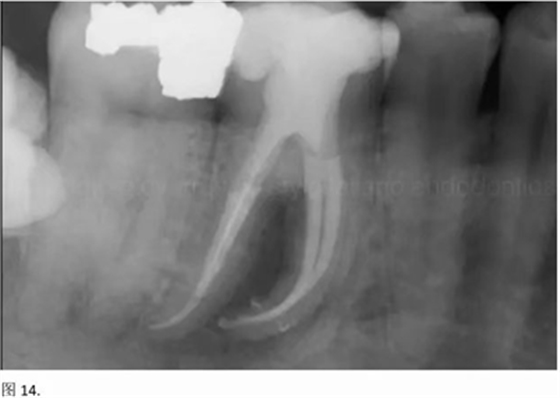

開髓后預敞、探查根管、建立直線通路是根管機械預備的第一步。在這些階段中,醫(yī)生可能會經(jīng)常遇到一些困難。這些難題包括器械折斷、臺階形成、根管歧坡或根管拉直、帶狀穿孔、根尖穿孔、根尖肘形、根尖堵塞。所有這些錯誤可導致根管系統(tǒng)清潔不完善從而降低牙髓治療成功率。

本文的目的是描述一種旨在優(yōu)化根管根尖部分預備的預敞技術(shù)。根管頸部或冠方的早期預敞對于減少初尖銼直徑和根尖部根管直徑之間的差異至關(guān)重要。大量研究表明,手用或機用器械預敞根管能顯著減少器械折斷的發(fā)生率。